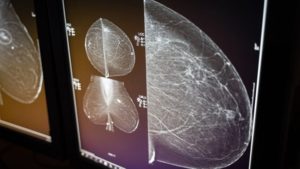

AI shows major promise in breast cancer detection, new studies suggest